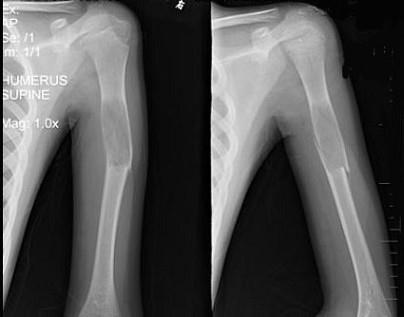

问题 13岁男性患者,因轻微外伤后感左肱骨上部疼痛,软组织肿胀,摄片见左肱骨上段局限性骨质沿髓腔膨胀性破坏,骨皮质变薄,部分骨皮质不连续,最可能的诊断是 ( )

选项 A、左肱骨巨细胞瘤伴病理性骨折 B、左肱骨嗜酸性肉芽肿伴病理性骨折 C、左肱骨骨囊肿伴病理性骨折 D、左肱骨骨纤伴病理性骨折 E、左肱骨骨折

答案 C